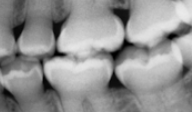

A mother brought in a child with concerns that their teeth appear to be “wearing away”. An x-ray was taken revealing the following. What is the likely cause?

A

dentogenesis imperfecta (because you can’t see the pulp chambers)